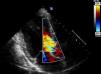

Caso clínicoDoente do género masculino, de 50 anos de idade, com antecedentes médicos de tabagismo, toxicodependência e hepatite C crónica, recorreu ao serviço de urgência por astenia, febre e cefaleia com um mês de evolução e dor abdominal desde há 2 dias. Ao exame objetivo o doente apresentava febre e a auscultação cardíaca evidenciou um sopro diastólico agudo, em decrescendo, grau iii/vi, ao nível do bordo esquerdo do esterno. O doente não apresentava sinais de insuficiência cardíaca. O estudo analítico demonstrou insuficiência renal aguda (Cr 2,5mg/dl, Ureia 60mg/dl, valores normais em análises efetuadas uma semana antes), elevação da proteína c-reativa (77,5mg/L) e anemia normocítica e normocrómica (Hb 11,2g/dl). Realizou tomografia computorizada (TC) abdominal que evidenciou esplenomegalia, não se visualizando áreas de enfarte, e hidroureteronefrose direita condicionada por aneurisma da artéria ilíaca comum direita com 42mm de maior diâmetro. Efetuado ecocardiograma transtorácico no qual se observou uma vegetação de 15mm na cúspide não coronariana da válvula aórtica (Figura 1) e insuficiência aórtica severa (Figura 2), com compromisso moderado a grave da função sistólica do ventrículo esquerdo (fração de ejeção de 35%), achados confirmados por ecocardiograma transesofágico. O doente foi internado no Serviço de Cardiologia, tendo iniciado antibioterapia empírica com vancomicina e meropenem. Foi decidido não introduzir aminoglicosídeo atendendo à taxa de filtração glomerular baixa, estimada em 20ml/min/1,73m2. No 2.° dia de internamento verificou-se lentificação cognitiva do doente, sem alterações neurológicas focais, tendo-se requisitado ressonância magnética (RM) cerebral, na qual foi possível observar múltiplos enfartes cerebrais recentes. As hemoculturas isolaram Candida albicans (C. albicans) sensível à anfotericina lipossómica, tendo-se iniciado terapêutica antifúngica e contactado o centro cirúrgico no sentido de transferir o doente para substituição valvular aórtica. Enquanto aguardava transferência, o doente iniciou dor súbita intensa no membro inferior esquerdo, com arrefecimento e perda de pulsos, constituindo um quadro de isquemia aguda do membro, de provável causa cardioembólica (vegetação micótica). Foi transferido para o centro de cirurgia vascular com urgência, onde realizou tromboembolectomia arterial femuro-distal esquerda. Posteriormente foi transferido para o centro de cirurgia cardiotorácica onde se procedeu à substituição da válvula aórtica por prótese biológica. O exame microbiológico da válvula aórtica e do êmbolo retirado da artéria femoral esquerda demonstraram crescimento de C. albicans. O ecocardiograma transtorácico pós-operatório evidenciou prótese aórtica normofuncionante, tendo sido transferido para o Serviço de Cardiologia deste hospital 14 dias depois. Durante o internamento apresentou febre e subida dos marcadores de inflamação. Repetiu o ecocardiograma transtorácico que confirmou a presença de prótese normofuncionante, sem evidência de vegetações. Realizou angio-ressonância magnética abdominal e dos membros inferiores, tendo sido identificado: volumoso pseudoaneurisma do eixo arterial ilíaco direito com oclusão da artéria ilíaca externa distal ao pseudoaneurisma; múltiplas tumefações compatíveis com abcessos na região inguinal e coxa esquerdas (local da abordagem cirúrgica vascular prévia); e abecedação do compartimento muscular ântero-lateral da perna esquerda (Figura 3). Atendendo à existência de foco infeccioso e ao ecocardiograma transtorácico sem evidência de endocardite, decidiu-se não repetir o ecocardiograma transesofágico. O paciente foi transferido para o Serviço de Cirurgia Vascular, tendo sido submetido a tratamento cirúrgico: aneurismectomia total com realização de pontagem femuro-femoral cruzada esquerda-direita com veia grande safena direita invertida, associado a exploração e drenagem dos abcessos na coxa e na perna esquerdas. O exame microbiológico do pseudoaneurisma evidenciou crescimento de Staphylococcus epidermidis (S. epidermidis). Durante o internamento no Serviço de Cirurgia Vascular o doente manteve febre intermitente e deterioração progressiva do estado geral. Repetiu hemoculturas que demonstraram crescimento de S. epidermidis, tendo iniciado antibioterapia de largo espectro com vancomicina e meropenem. Realizou TC pélvico e das coxas identificando-se 2 novos pseudoaneurismas: na artéria ilíaca interna esquerda e na artéria femoral superficial esquerda. O paciente foi novamente submetido a tratamento cirúrgico: durante o procedimento constatou-se a rápida progressão da situação clínica, havendo rotura do pseudoaneurisma femoral esquerdo, com extensa infiltração hemorrágica e abcedação da coxa. Procedeu-se a laqueação das artérias ilíaca interna esquerda e femoral superficial esquerda, associado a desbridamento alargado de tecidos desvitalizados e de coleções purulentas. Em tempo cirúrgico deferido procedeu-se a amputação transfemoral aberta, por ter havido progressão para gangrena da perna. Durante o internamento prolongado no Serviço de Cirurgia Vascular, de cerca de 4 meses, o doente manteve sempre terapêutica antifúngica e foi submetido a reamputação transfemoral e a vários desbridamentos cirúrgicos de abcessos do coto. Após o encerramento parcial do coto o doente obteve alta, clinicamente estável, tendo-se decidido não manter antifúngico devido à hepatite C crónica que o doente apresentava e à possível toxicidade hepática dos antifúngicos.